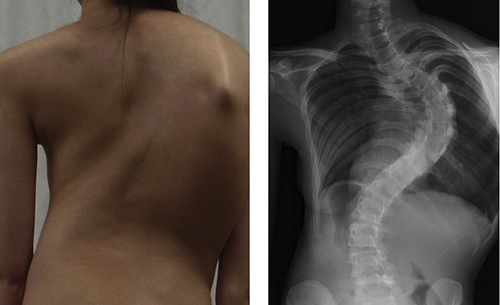

Girl with adolescent idiopathic scoliosis (left) and posterior-anterior standing x-ray of spine (right)

AIS is the most common pediatric skeletal disease, affecting approximately 2% of school-age children. The causes of scoliosis remain largely unknown and brace treatment and surgery are the only treatment options. However, many clinical and genetic studies suggest a contribution of genetic factors.